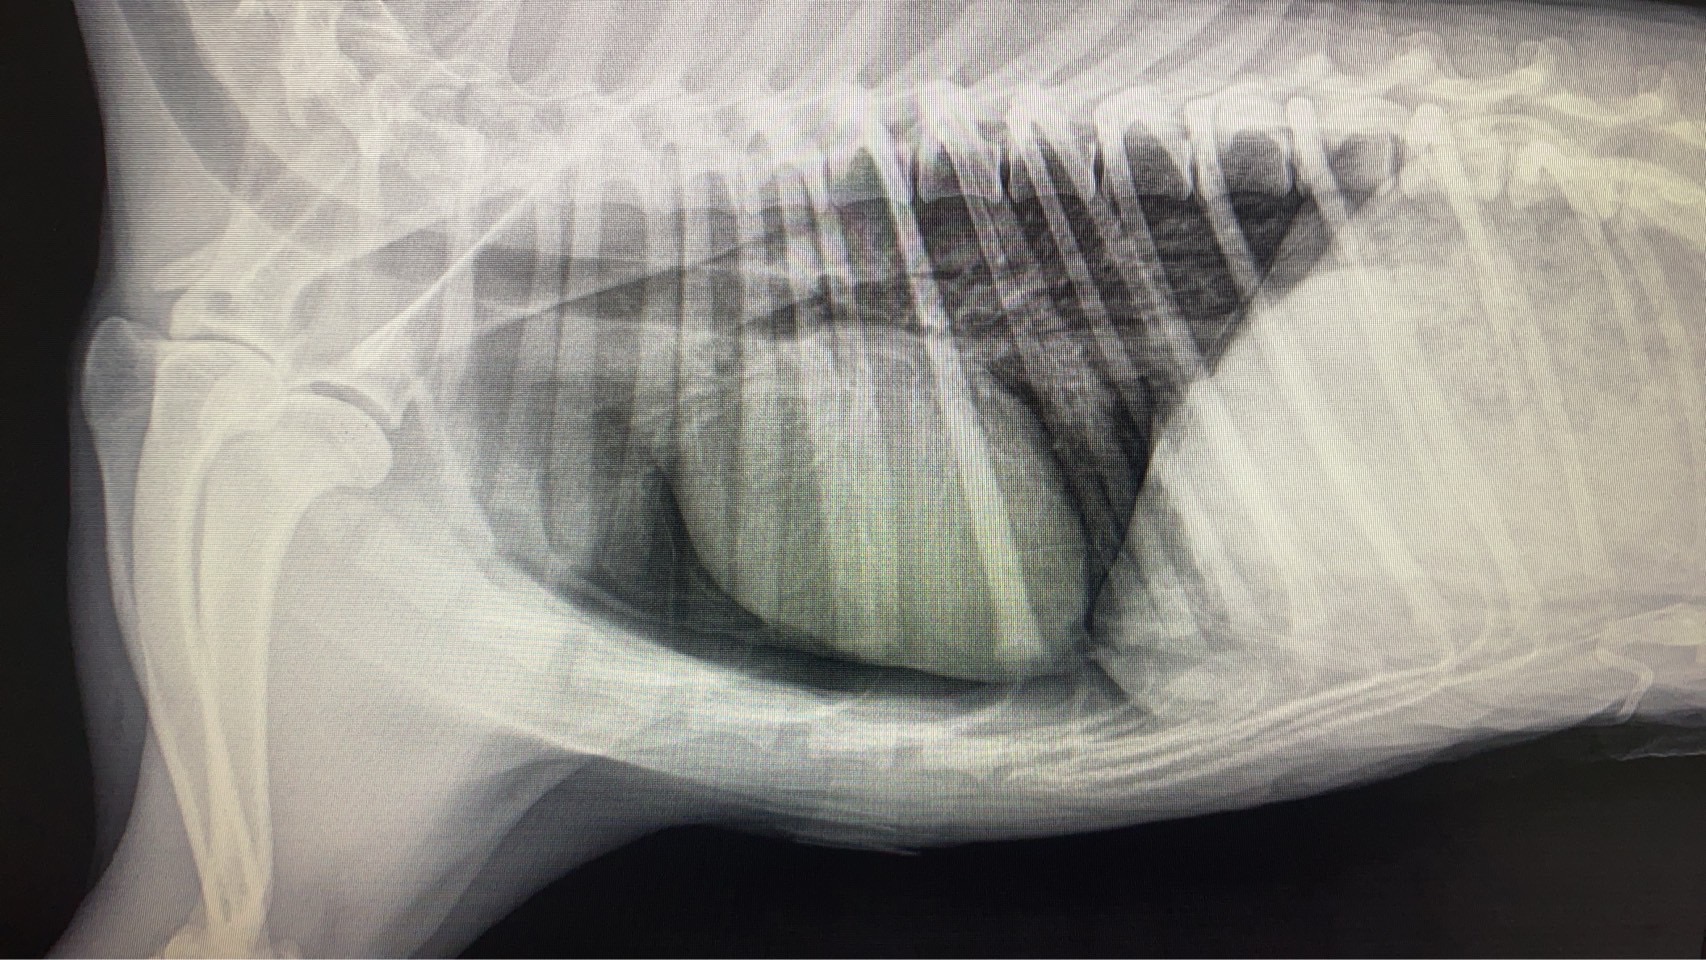

ทีมสัตวแพทย์ของเราได้รับเคสฉุกเฉินจากอุบัติเหตุที่ทำให้สัตว์เลี้ยงตัวหนึ่งได้รับบาดเจ็บรุนแรง กะบังลมฉีกขาดส่งผลให้อวัยวะในช่องท้องเคลื่อนเข้าไปในช่องอก ทำให้เกิดภาวะหายใจลำบาก หลังจากตรวจวินิจฉัยด้วยภาพรังสี ทีมสัตวแพทย์ได้ตัดสินใจเข้าผ่าตัดแก้ไขโดยการเย็บกะบังลม และจัดอวัยวะกลับสู่ตำแหน่งปกติ ผลลัพธ์เป็นที่น่าพอใจ น้องสามารถหายใจได้ตามปกติและกลับมาใช้ชีวิตได้อย่างมีความสุข โรงพยาบาลสัตว์ของเราพร้อมดูแลสัตว์เลี้ยงทุกตัวด้วยทีมแพทย์ผู้เชี่ยวชาญ หากพบอุบัติเหตุหรือภาวะฉุกเฉิน